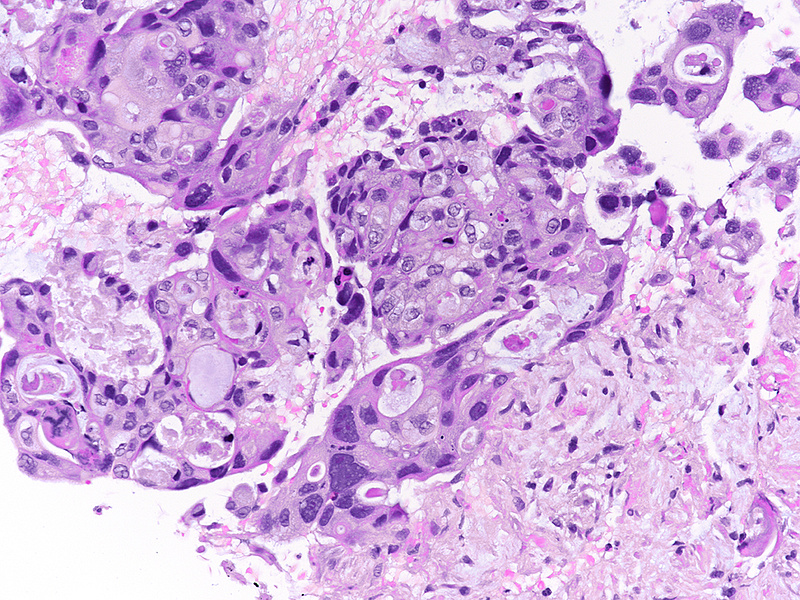

The well-sampled biopsy showed fragments of a necrotising carcinoma, arranged in isolated cells, small aggregates of cells and poorly formed glandular structures (Panels A-B). The tumour cells demonstrated abundant eosinophilic cytoplasm and severely pleomorphic, hyperchromatic nuclei with distinct nucleoli. Brisk mitotic activity was noted (Panel C). Within some clusters, the neoplastic cells had a more polygonal appearance, with intercellular desmosomes, more basophilic cytoplasm and evidence of dyskeratosis (Panels D-E).

By immunohistochemistry, the tumour cells were strongly and diffusely positive for CK7 (Panel F), focally positive also for p40 (Panel G) and CK20 (not shown). Ki67 labelling index confirmed the suspected high proliferation rate, estimated between 40-50% (Panel H). The immunohistochemical screening for DNA mismatch repair (MMR) deficiency showed no loss of protein expression. A final diagnosis of poorly (to undifferentiated) adenocarcinoma of the pancreas with squamous differentiation (consistent with adenosquamous carcinoma) was made.